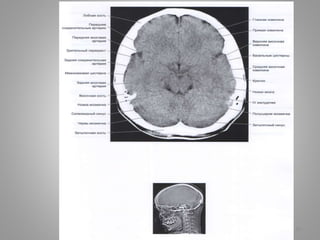

• #15 Велика цистерна

• #16 Передмоства цистерна Мосто-мозочкова цистерна

• #17 Міжніжкова цистерна Базилярні цистерни

• #18 Охоплююча цистерна

• #19 Охоплююча цистерна

• Велика (мозочково-мозкова) цистерна (cisterna magna, c. cerebellomedullaris) –

сама велика цистерна, яка обмежена мозочком, довгастим мозком та потиличною

кісткою.

• Цистерна моста (препонтинна) - розташовується наперед від моста мозку, містить

базилярну артерію. Зєднується позаду з мосто-мозочково-мозковою цистерною та

субарахноідальним простором спинного мозку, попереду – з міжніжковою

цистрною.

• Базальна цистерна (c. suprasellar) має п'ятикутну форму, включає міжніжкову

цистерну (між ніжками мозку) і цистерну перехреста (між перехрестом зорових

нервів і лобними частками).

• Чотиригорбкова цистерна (вени Галена) (c. quadrigeminalis) розташовується між

мозолистим тілом і мозочком; у її ділянці можуть розташовуватись

субарахноідальні кисти

• Обвідна (охоплююча; по Синельникову - обхідна) цистерна (c. ambient) - канал

неправильної форми, що проходить по бокам ніжок мозку і даху середнього

мозку; сполучається з мостовою і міжніжковою цистернами спереду і

чотирегорбиковою цистерною ззаду.

• Цистерна бічної ямки великого мозку (cisterna fossae lateralis cerebri) -

розташовується в латеральній борозні великого мозку.